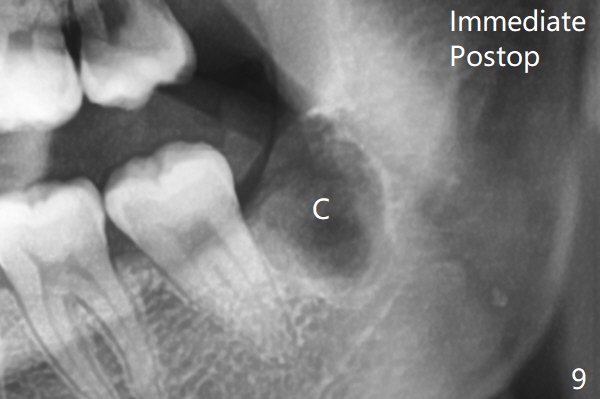

原来右下牙槽窝放置骨胶原塞(Osteogen Plug),而左下胶原塞。

塞的密度       Last     Next   智齿拔除